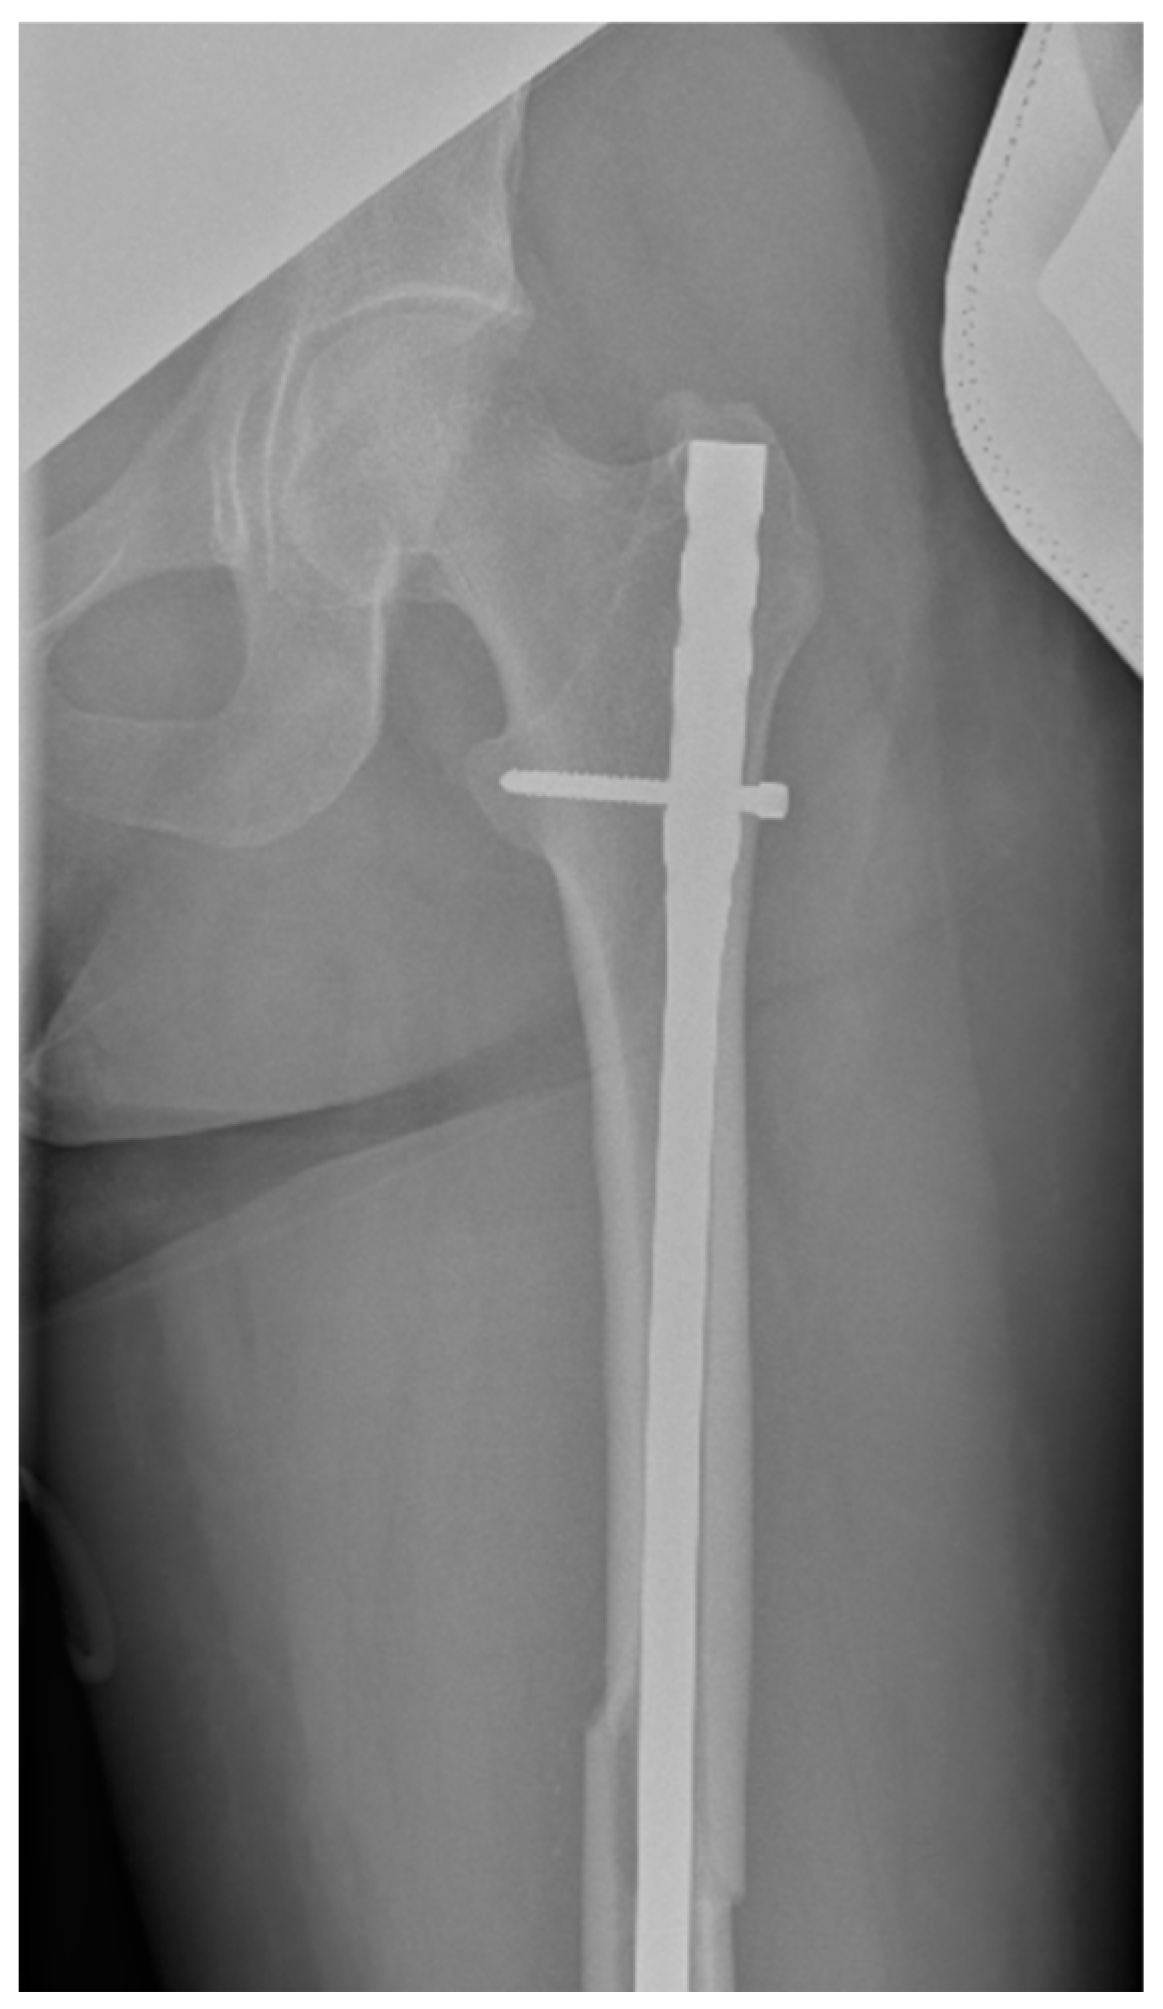

Surgical intervention was performed by a multidisciplinary team: an anesthetist, an obstetrician, a neonatologist, and an orthopedist. She underwent spinal anesthesia utilizing 0.5% bupivacaine, with the extraction of a healthy female baby, weighing 3200 g, with an Apgar score of 9 by C-section and bilateral tubal ligation at the request of the patient, followed by a successful fracture repair under intraoperative C-arm fluoroscopy. The surgical intervention for the fracture of the femur consisted of closed reduction and osteosynthesis with an anterograde intramedullary nail locked proximally and distally with a screw. The postoperative X-ray control revealed good fracture reduction and correct placement of the osteosynthesis material (Figure 2 and Figure 3).

Figure 3.

Postoperative anteroposterior view of the left thigh—distal pole of the intramedullary anterograde nail fixed statically with one screw.